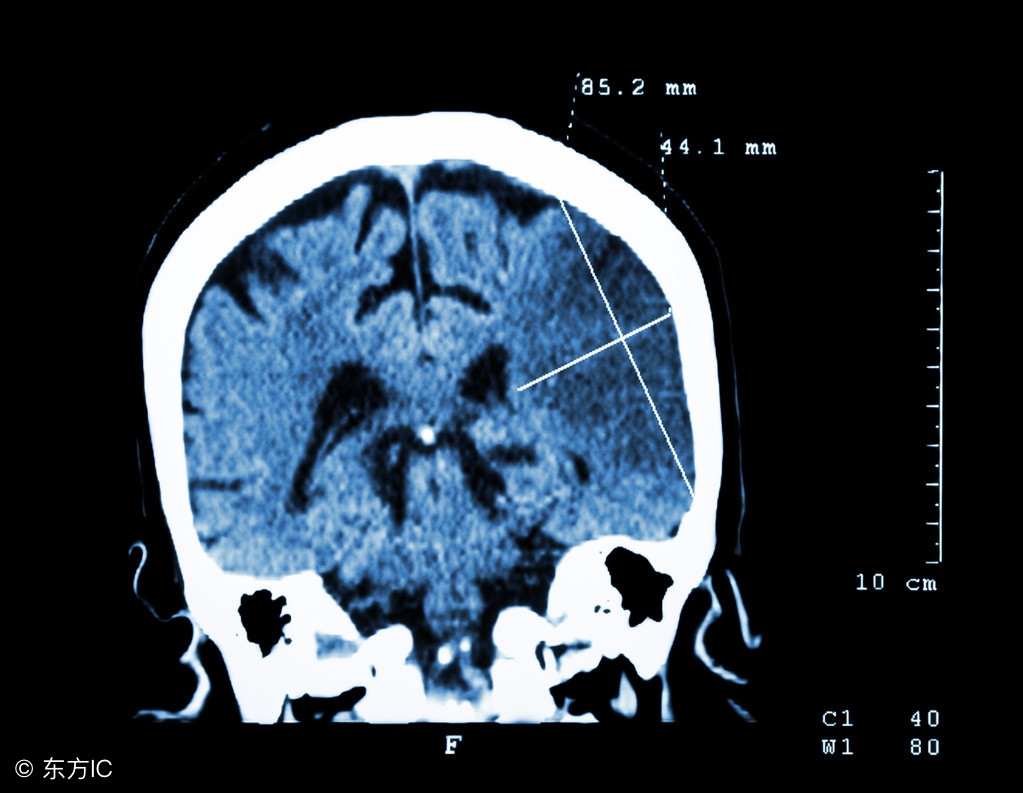

(3)降低颅内压和脑水肿,急性特别是大面积脑梗塞时可出现脑水肿,是发病后1周内死亡的常见原因。